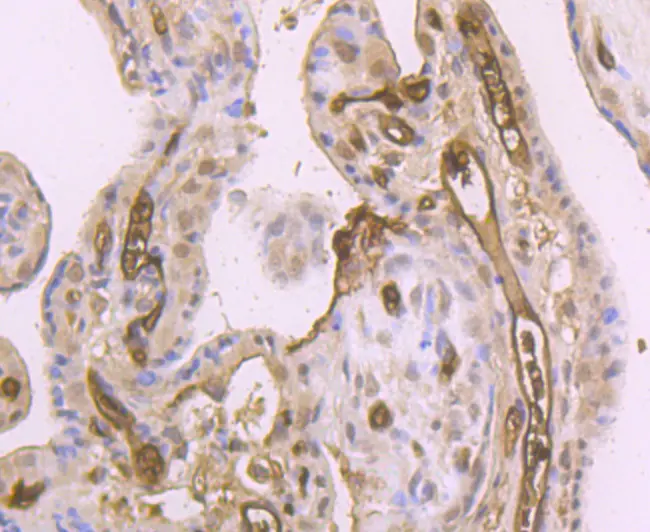

DKK1主要由成骨细胞、骨细胞分泌,其次也表达于很多组织和细胞类型,包括胎盘、皮肤、前列腺、血管内皮、肾脏、成骨细胞和骨细胞等多个部位。DKK1作为一种分泌型糖蛋白,主要通过与Wnt蛋白竞争性结合LRP5/6受体,拮抗Wnt/β-catenin信号通路活性,调节细胞增殖、分化及癌变,影响细胞凋亡、瘤细胞侵袭和转移。越来越多的研究证实DKK1在肿瘤发生发展中呈现多样化的特点,甚至在同一种细胞中,因生理环境不同表现出相反的调节作用,其功能相对较复杂。人类Dkk-1转录物大量存在于胎儿肾脏、成人胎盘和成人前列腺中。Dkk-1起始位点上游的假定顺式调控元件包括p53、Sp1、MyoD、STAT、Oct-1/2、C/EBP-a、C/EBP-b、GATA-1、GATA-2和GATA-3。

染色定位

细胞质

阳性对照

胎盘、前列腺、肝脏、子宫内膜